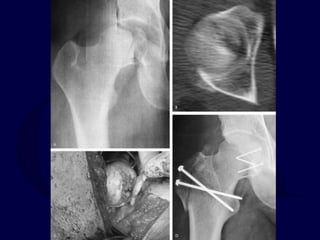

2. Hip Dislocation with Femoral

Neck Fracture

Usually the dislocation is posterior.

Thus, Kocher-Langenbeck approach.

If fracture is non-displaced, stabilize fracture

with parallel lag screws first.

If fracture is displaced, open reduction of

femoral head into acetabulum, reduction of

femoral neck fracture, and stabilization of

femoral neck fracture.